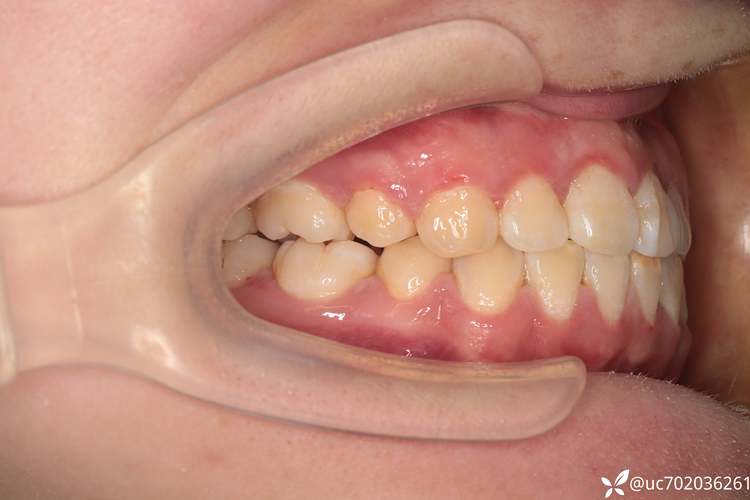

视频开头常呈现医生对患者口腔的全面检查:包括口内照(显示牙齿排列、前突程度)、X光片(头颅侧位片观察颌骨关系、牙根位置)、口内扫描(获取牙齿3D模型,模拟排齐效果),关键画面是医生通过头影测量数据讲解,如“SNA角(上颌骨相对于颅骨的位置)正常,但牙齿前突量达10mm,需拔除4颗第一前磨牙,为前牙内收提供12-14mm空间”,此阶段视频会强调“个性化方案”,避免患者误认为“所有龅牙都要拔牙”。

- 关闭拔牙间隙(6-12个月):随着牙齿排齐,更换较粗的镍钛丝(0.018英寸)或不锈钢方丝,通过“滑动法”或“关闭曲法”内收前牙,视频特写弓丝上的“滑动槽”,医生用结扎丝将牙齿与弓丝固定,随着前牙逐渐向内移动,拔牙间隙逐渐缩小(此阶段是改善龅牙侧貌的关键,视频会对比前牙内收过程中的唇部变化)。

效果展示:直观对比治疗前后面型

视频结尾通常展示患者的治疗前后对比:口内照可见牙齿从拥挤、前突变为整齐、排列整齐;面部照可见嘴唇不再外翻,侧面轮廓更流畅,“鼻-唇-颏”协调性改善;部分视频还会拍摄患者治疗后的采访,如“以前不敢大笑,现在可以自信露齿笑了”。